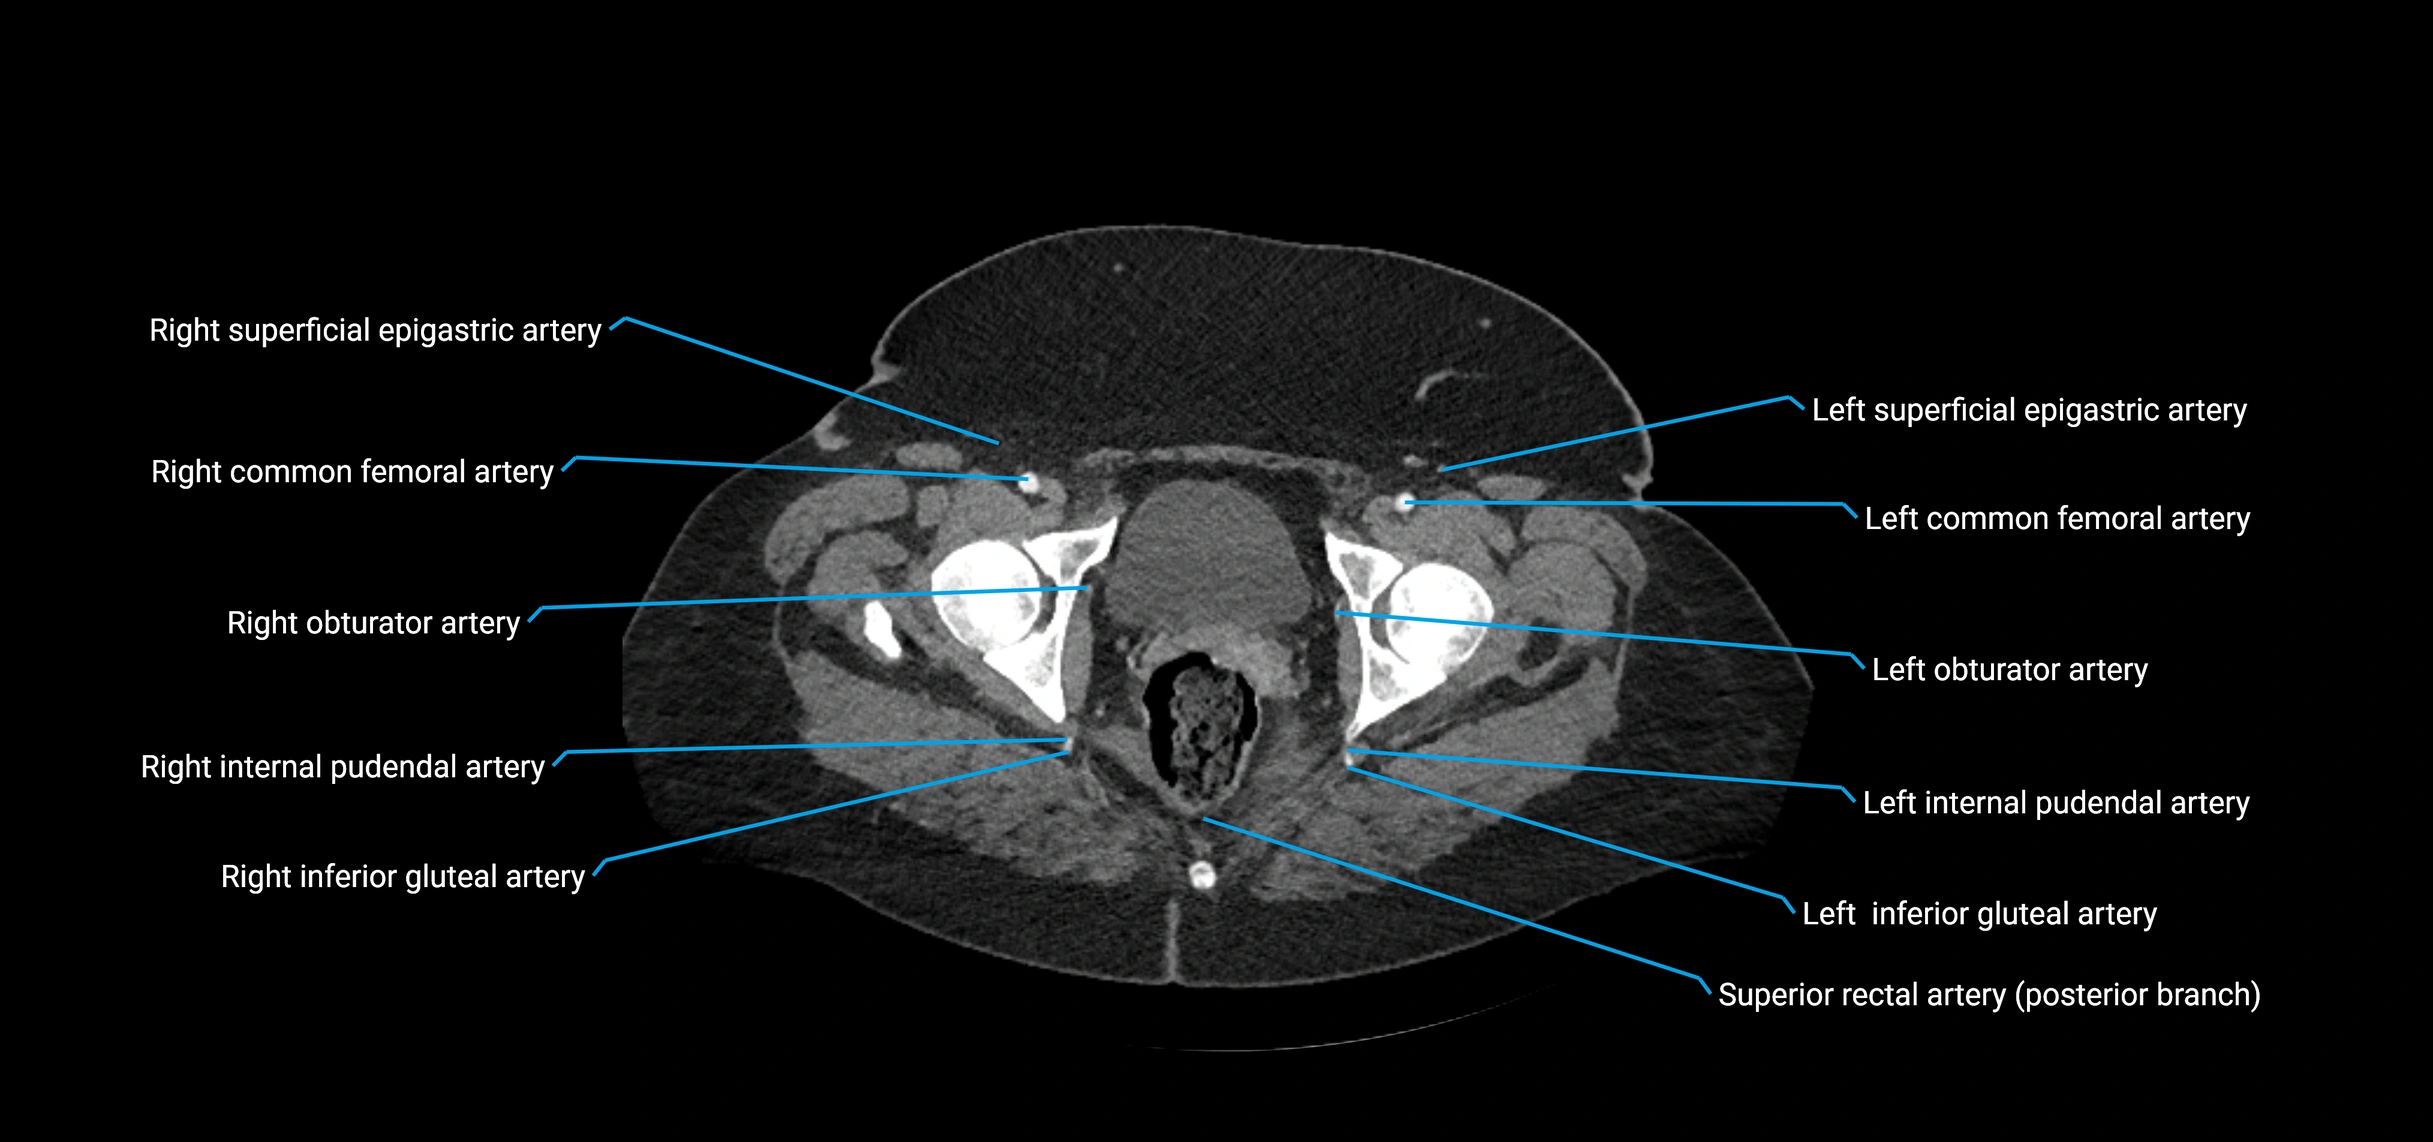

Contrast-enhanced CT (CTA):

• Gold standard for abdominal aortic imaging

• Provides excellent detail of lumen, wall, aneurysm, thrombus, and branch vessels

• Multiplanar and 3D reconstructions help in aneurysm measurement, stent graft planning, and dissection evaluation

• Detects acute rupture, traumatic injury, or occlusion with high sensitivity